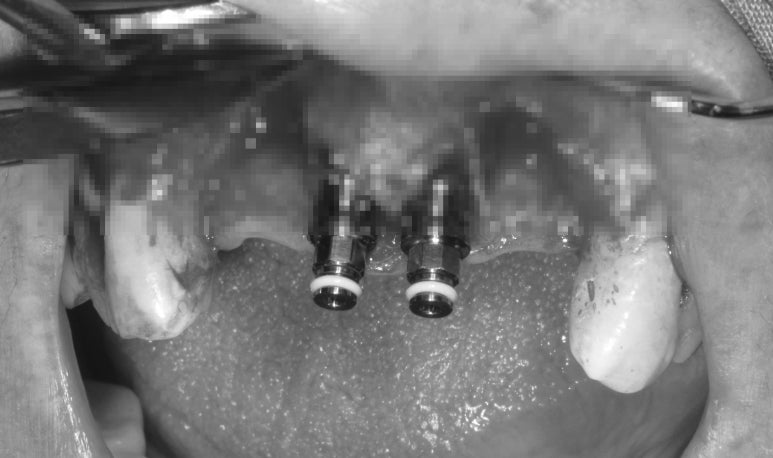

이렇 식으로 예쁘게 두개의 임플란트가 위치되었습니다.

상당히 넒은 부위에 두개만 있으니 뭔가 허전하네요..ㅠㅠ

실밥제거를 하였습니다.

아직도 아파보이셔서 속상합니다. ㅠㅠ

실밥제거를 하고 보니 잇몸 색은 많이 돌아온 것을 볼 수 있었어요. 정상치유과정을 거치고 있습니다.

하얗게 보이는 것이 위에서 소개했던 비흡수성 차폐막 cytoplast입니다.